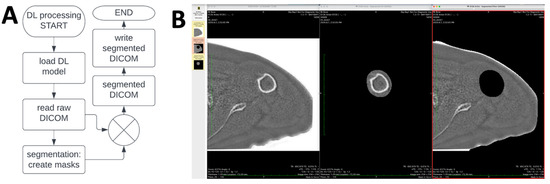

2.6. Clinically Applicable DL Segmentation Workflow

In addition to the development of the DL segmentation model, additional processing steps were developed to create a workflow that can be used on an MRI scanner, without the need for off-line processing. As shown in the flowchart in Figure 5A, a MATLAB runtime (R2021b for Linux) program was compiled as binary and installed on an MRI console to: (1) read inverted ZTE DICOM images; (2) perform DL segmentation (using the same routine as the off-line version) to create masks of the humeral head/humerus and the remaining tissues; and (3) multiply with input ZTE images to create a new series of images showing the separated structures viewable on the MRI console or any PACS (Figure 5B). This enabled a push-button DL segmentation of ZTE shoulder images directly on the MRI scanner for an immediate evaluation following acquisition. As a quality control measure, we compared the DICOM images from the MRI console to the those from off-line programs and found no difference in the images.

Figure 5.

(A) Flow chart of ZTE DL processing, which reads raw digital imaging and communications in medicine (DICOM) images, and performs DL segmentation to create masks for the humerus and the remaining tissues. The masks are then multiplied with the raw image to create segmented DICOM images that are saved as a new series in the exam. (B) Segmented DICOM images viewed in a PACS viewer, showing the original image on the left, the segmented humeral bone in the middle, and segmented remaining tissues on the right.